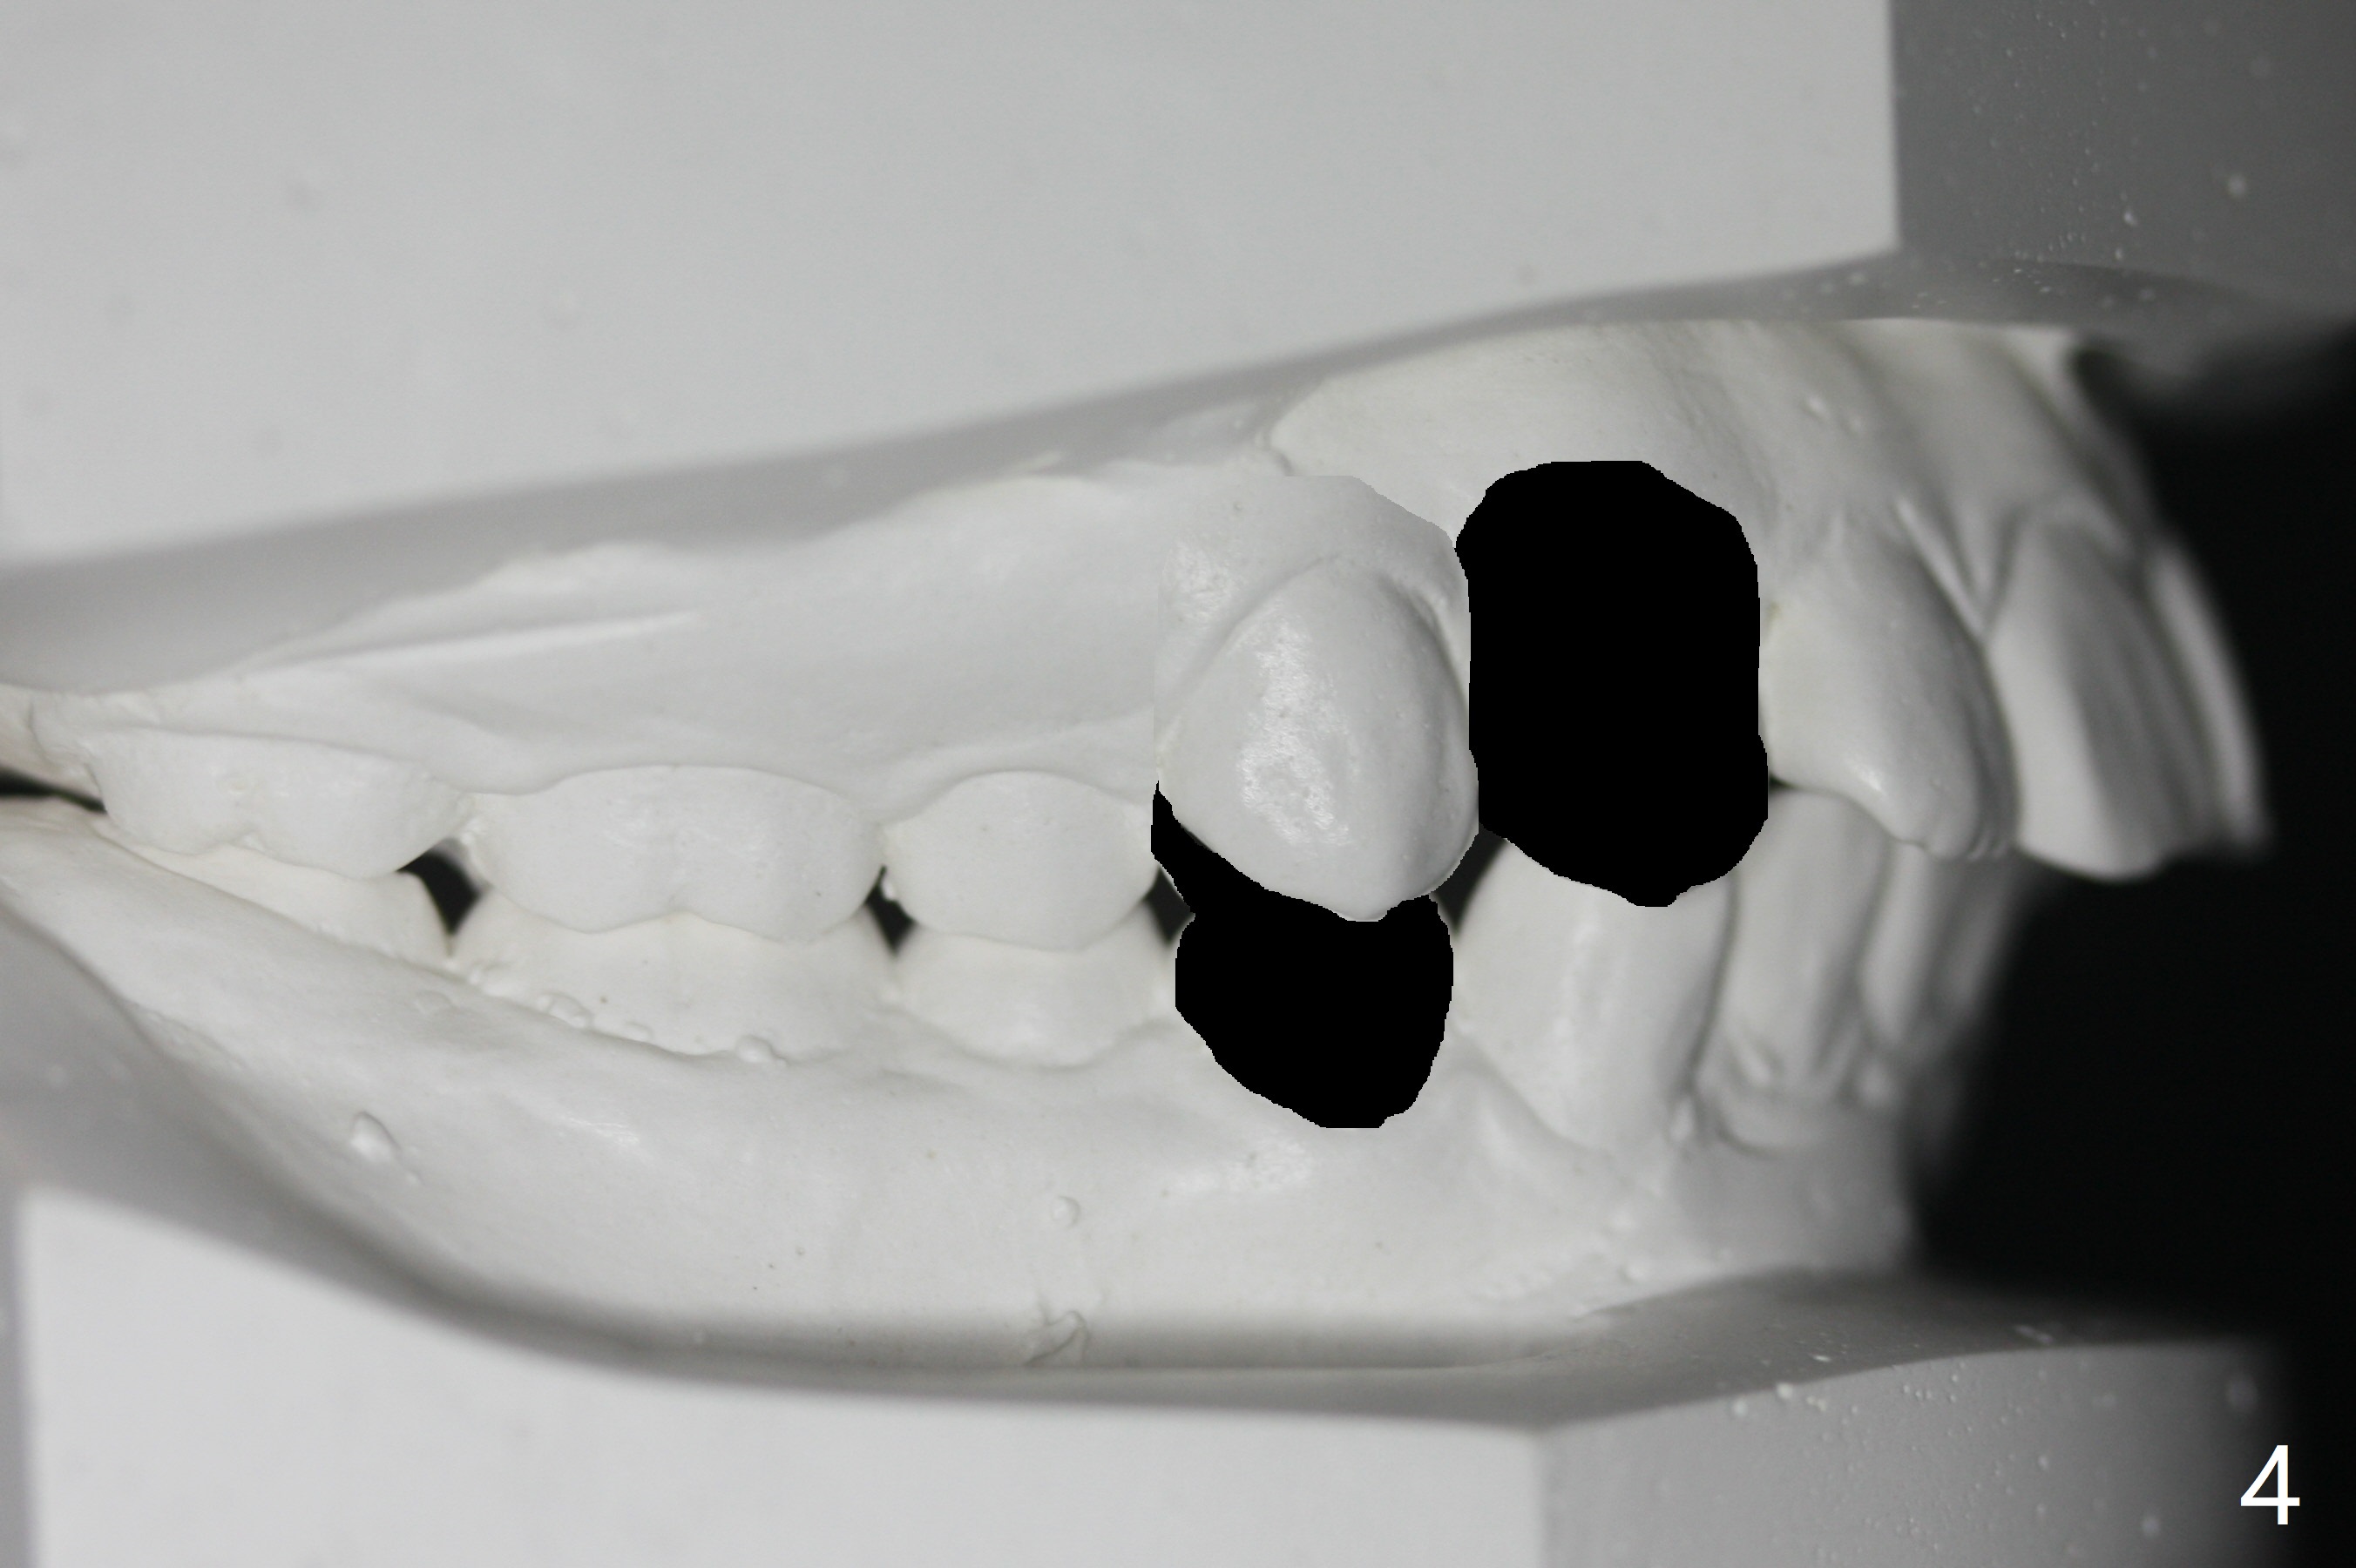

I Malocclusion

The 1st step to correct severe Class II Division I malocclusion (Fig1) is extraction of 4 of the 1st bicuspids (Fig.2 X). Following placement of 16x16 wires, start Class II retraction (Fig.3 red line) as well as distalization of U3 (Fig.4). When canine Class I relation is established (Fig.5 horizontal arrow (using power chain between L3/5)), arch wire sequence should be able to intrude the incisors (vertical arrows). Finally the lower 2nd bicuspid and molars are mesialized (Fig.6 arrow).